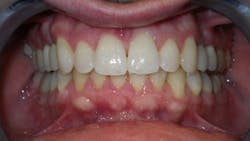

Everything added up to a diagnosis of maxillary deficiency, which had an adverse effect on the position of the mandible. The patient’s narrow, underdeveloped maxilla also trapped his mandible in a retruded position upon closure.

Again, the above diagnostic information was taken into consideration during the consultation process. Since the patient had both foundation and tooth alignment issues, it was determined that he would benefit from a treatment plan addressing both issues. An upper removable expansion appliance would be a good choice to start; however, this patient knew he would not be able to achieve the compliance necessary for the appliance to be effective. Fortunately, clear aligners offer an excellent opportunity for arch development, tooth alignment, and a healthy occlusion.